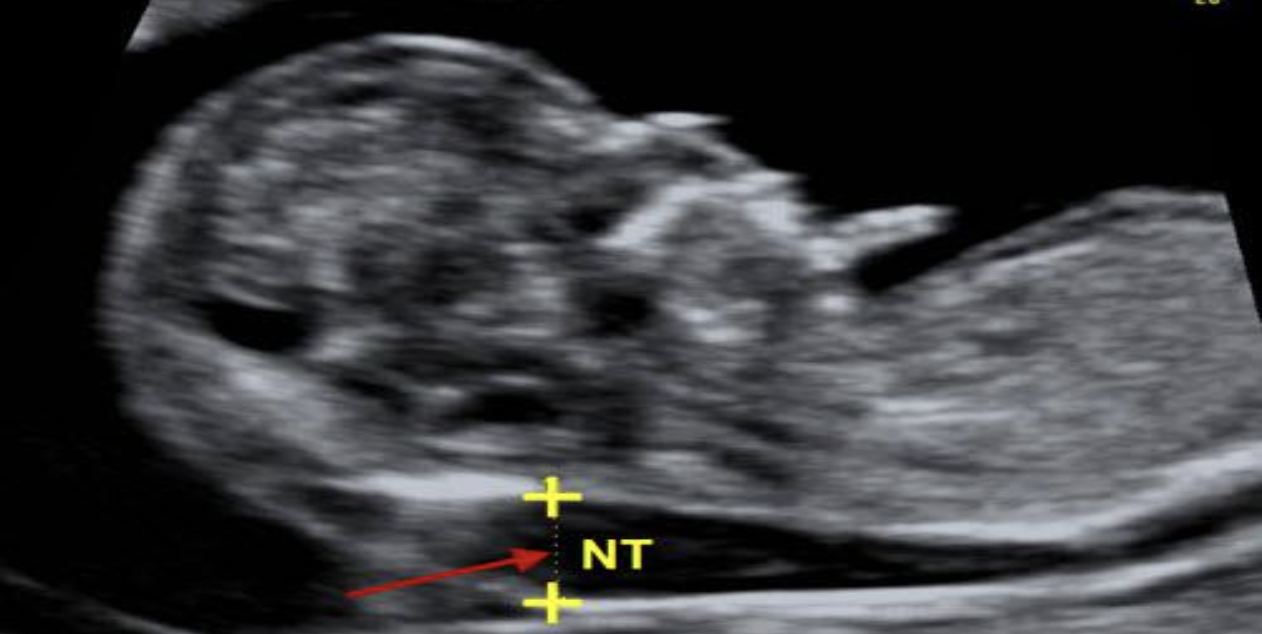

Độ mờ da gáy (NT) là gì?

Độ mờ da gáy (NT) là vùng giảm âm nằm giữa da và các mô mềm phía sau cột sống cổ của thai nhi. Khoảng giảm âm này được cho là đại diện cho tình trạng phù nề trung mô và thường liên quan đến hệ bạch huyết. NT có thể được xác định ở hầu hết thai nhi trong giai đoạn từ tuần 11 đến tuần 14 của thai kỳ.

Đo độ mờ da gáy trên siêu âm

Ở những thai nhi bình thường, NT tăng nhẹ thường có thể tự hết trong tam cá nguyệt thứ hai. Tuy nhiên, khi NT tăng nhiều hoặc tồn tại kéo dài, đây có thể là dấu hiệu gợi ý những bất thường tiềm ẩn.